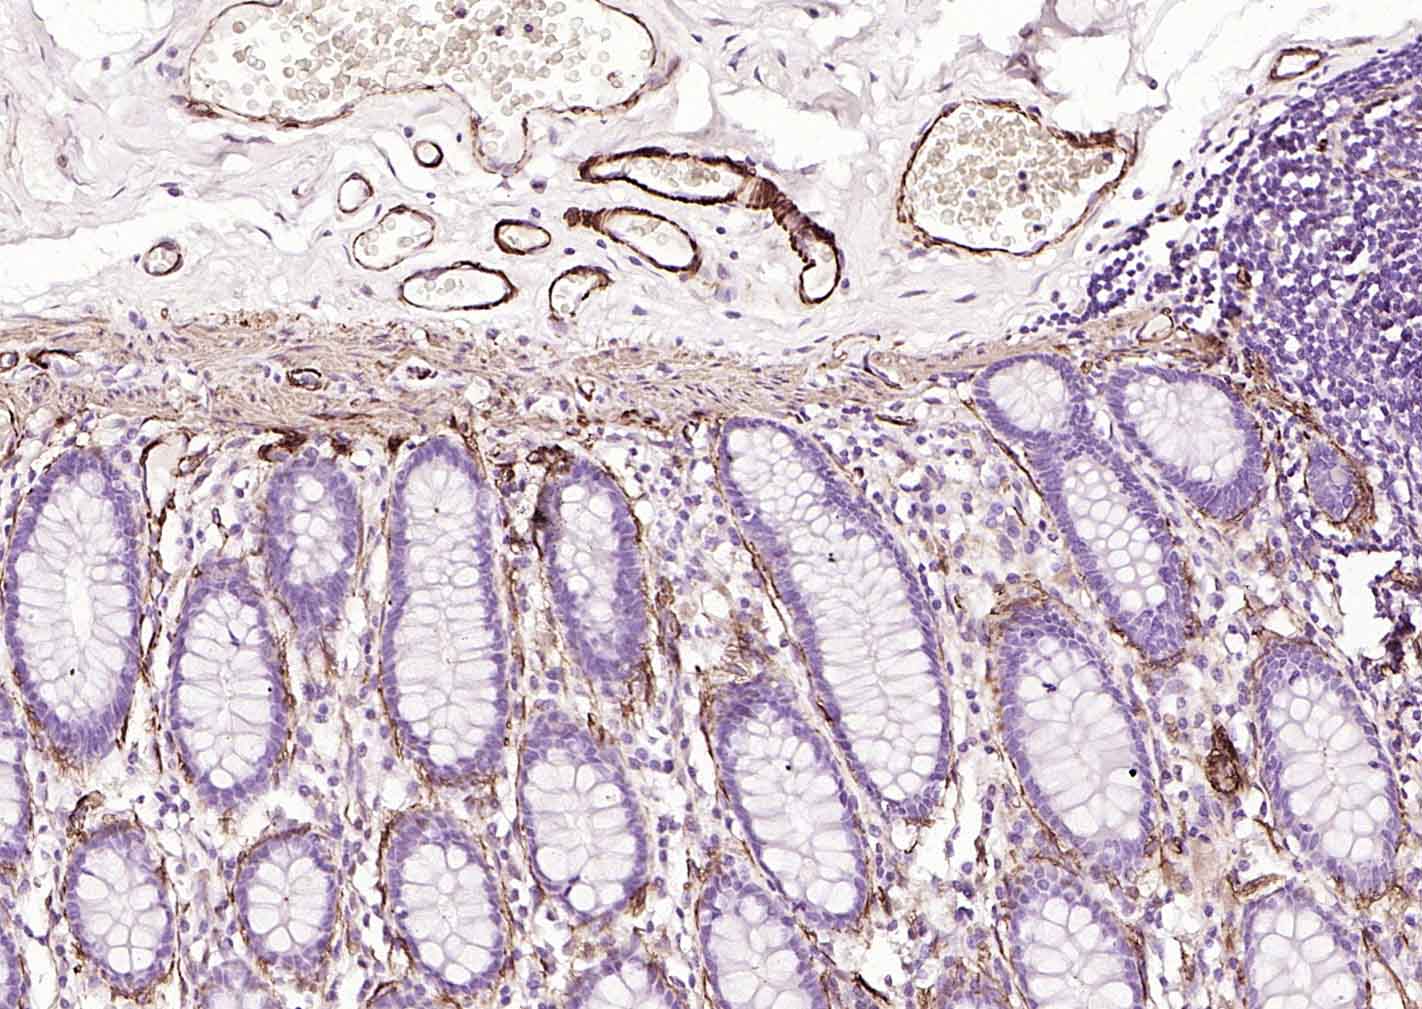

產(chǎn)品圖片

Paraformaldehyde-fixed, paraffin embedded (human colon); Antigen retrieval by boiling in sodium citrate buffer (pH6.0) for 15min; Block endogenous peroxidase by 3% hydrogen peroxide for 20 minutes; Blocking buffer (normal goat serum) at 37°C for 30min; Incubation with (Caldesmon/CDM) Monoclonal Antibody, Unconjugated (bsm-60918R) at 1:200 overnight at 4°C, followed by operating according to SP Kit(Rabbit) (sp-0023) instructionsand DAB staining.